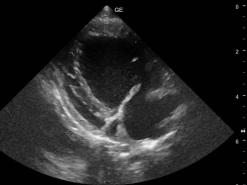

Mit dem Ultraschall werden der Herzmuskel und seine Anhänge dargestellt. Die verdickten Klappenteile, das Ausmass des Pendelblutes, der vergrösserte Vorhof und Ventrikel sowie die Druckdifferenzen sind mess- und darstellbar. Nach dieser systematischen Erfassung und Beschreibung beurteilt die Tierärztin den Schweregrad der Erkrankung und definiert Therapie-Optionen.

Deutlich vergrösserter linker Vorhof und Ventrikel

Vergrösserter Vorhof-Ventrikel und verdickte Klappen.